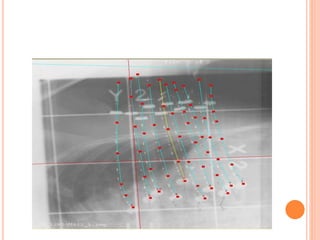

INTERSTITIAL BOOST

INTERSTITIAL IMPLANT

 Women with large breasts & deep seated tumors (>4cm

below skin)

 Surgical clips to localize & define every extension of

cavity – 6 clips suffice –med , lat , sup , inf , cephalad ,

caudal

 Higher dose can be delivered more easily at depth with

implant

 Source used – Ir192 by LDR or HDR

DESIGN OF THE IMPLANT GEOMETRY

 Needles are implanted parallel and equidistance from

each other.

 In most cases inserted in a mediolateral direction.

 In very medially or laterally located tumor sites, needles

should be implanted in a craniocaudal direction .to

enable separate target area from skin points.

 In some rare cases, the upper outer quadrant has to be

implanted with needles orientated in a 45° angle to

avoid overlap of source positions and skin

 2 planes of needles are usually needed to cover the

PTV.

 A single plane may be sufficient in case of a target

thickness of less than 12 mm.

 Three planes are required in a large breast where

the targeted breast tissue between pectoral fascia

and skin is thicker than 30 mm.

 15-25 needles spaced 15–20 mm are usually

required.

 Reference needle is first implanted at the posterior

(deepest) side into the centre of the PTV.

 For definitive positioning, the needle should pass

about 5 mm behind the internal scar.

 The other needles of the posterior plane are then

implanted parallel to the first one.

 Total number of

catheters based on

size of the seroma

cavity

 15 and 25 catheters

Connected to HDR